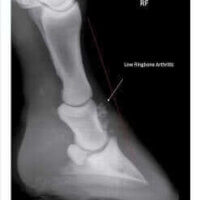

Joint disease in the horse is the number one cause of ongoing lameness and a result of many factors including excessive or ongoing trauma, genetics, diet and lifestyle influences. Degeneration within the joint leads to cartilage erosion, remodeling of the joint, ongoing pain and reduced range of motion in more severe cases. It is a condition that is best prevented and managed in the early stages versus in the advanced stages.